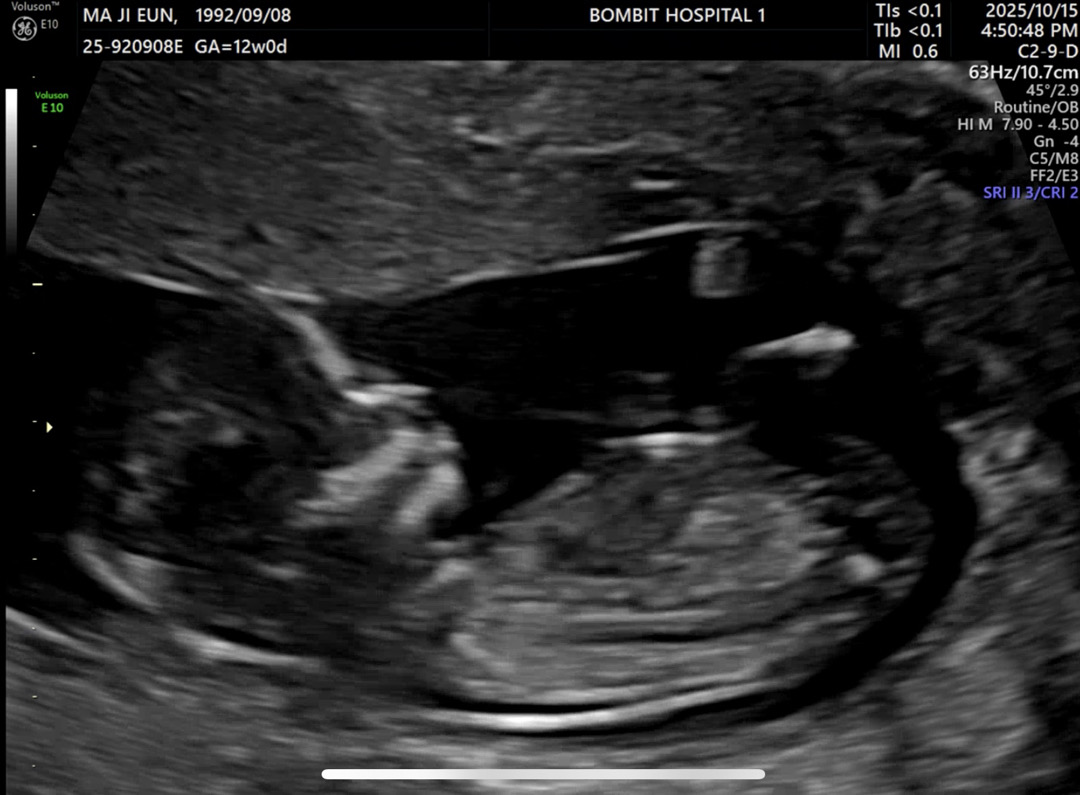

12주 각도법 보이시나요??🤔

베이비빌리 어플에서는 딸 같다는데 아들도 원해서 너무 궁금해요!! 어때보이나요?